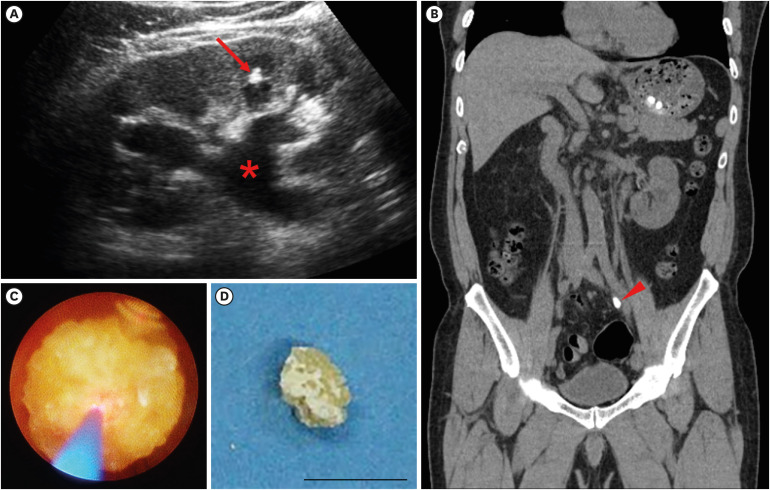

Cystinuria is an autosomal recessively inherited genetic disorder, and is typically classified into type A, caused by mutations in SLC3A1, or type B, caused by mutations in SLC7A9. While the predominance of the genotypes varies among countries, due to lack of a large scale cohort, the characterization of mutations in SLC3A1 or SLC7A9 is still limited in East Asia. A 61-year-old male patient admitted to the department of nephrology, with a chief complaint of fever, chillness and left flank pain for a week. The patient had a past history of recurrent urolithiasis, with a frequency of at least 1 to 2 times a year. Computed tomography visualized 1 cm-sized stone at distal ureter, which was removed by retrograde ureteroscopy. The stone analysis documented 100% of cystine, indicating an underlying genetic disorder, cystinuria. Whole genome sequencing from peripheral blood unveiled 3 heterozygous missense mutations in coding exons of SLC3A1 gene, and 2 heterozygous missense mutations in coding exons of SLC7A9 gene. We here report a case of cystinuria with compound heterozygous mutations both in SLC3A1 and SLC7A9 genes, with a total of 5 mutant alleles in a patient.